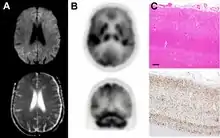

Imaging of the brain may be performed during medical evaluation, both to rule out other causes and to obtain supportive evidence for diagnosis. Imaging findings are variable in their appearance, and also variable in sensitivity and specificity.[43] While imaging plays a lesser role in diagnosis of CJD,[44] characteristic findings on brain MRI in some cases may precede onset of clinical manifestations.[45]

Brain MRI is the most useful imaging modality for changes related to CJD. Of the MRI sequences, diffuse-weighted imaging sequences are most sensitive.[46] Characteristic findings are as follows:

Brain FDG PET-CT tends to be markedly abnormal, and is increasingly used in the investigation of dementias.

- Patients with CJD will normally have hypometabolism on FDG PET.[50]

Histopathology

Testing of tissue remains the most definitive way of confirming the diagnosis of CJD, although it must be recognized that even biopsy is not always conclusive.[51]

The classic histologic appearance is spongiform change in the gray matter: the presence of many round vacuoles from one to 50 micrometers in the neuropil, in all six cortical layers in the cerebral cortex or with diffuse involvement of the cerebellar molecular layer.[54] These vacuoles appear glassy or eosinophilic and may coalesce. Neuronal loss and gliosis are also seen.[55] Plaques of amyloid-like material can be seen in the neocortex in some cases of CJD.[56]